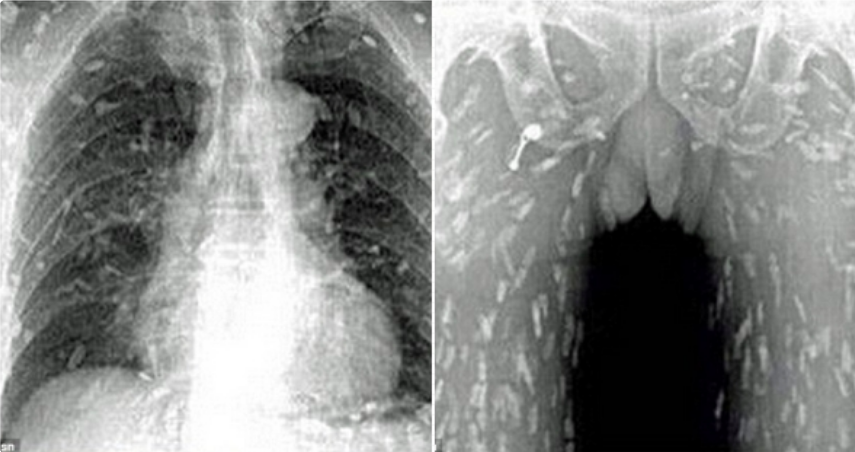

▼這張X光片中的景象可說是讓人看的頭皮直發麻!據稱,這是一名中國男子在吃了生魚片後全身發癢,到醫院求診後所拍下的,全身上下到處都是「白點」,成群條蟲游走全身,光是想像就讓人頭皮發麻。

▼男子在就醫後被轉往廣州市第八人民醫院,醫生認為他應是吃了受到污染的生魚片才會被條蟲寄生。條蟲只存在淡水魚類中,生魚片中非常常見的「鮭魚」便是其中一種。